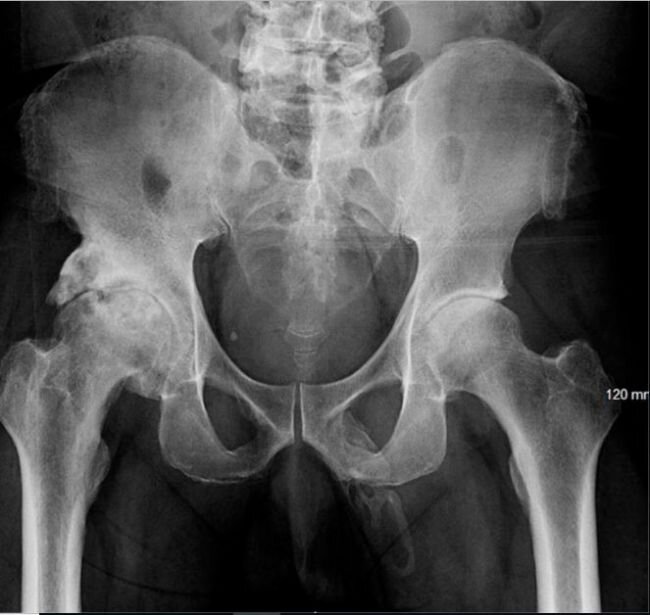

Проведя физический осмотр и выслушав жалобы пациента, доктор решает сделать рентген костей таза, чтобы исключить переломы. К счастью, переломов там не оказалось, но перед глазами врача предстала куда более удивительная картина.  Глядя на снимок доктор заметил некое окостенение вдоль всего ствола полового члена, иными словами, внутри пениса выросла кость.

Проконсультировавшись с коллегами, мужчине был поставлен диагноз "оссификация полового члена". По словам авторов докладов из медицинского центра психического здоровья им. Линкольна в Бронксе, Нью-Йорк, всего зарегистрировано не более 40 случаев подобного заболевания.